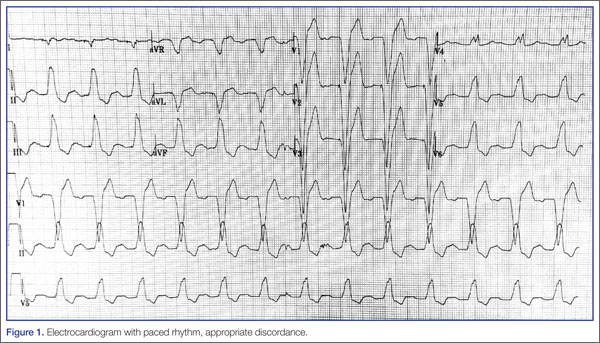

Because of the underlying rhythm induced by the cardiac pacemaker stimulation, acute coronary occlusion can be subtle.12 Since the pacemaker depolarizes the right ventricle, the delay in left ventricular depolarization is seen as left bundle branch block (LBBB) on electrocardiogram (ECG).13,14Figure 1 shows an ECG demonstrating paced rhythm and appropriate discordance, while the ECG in Figure 2 demonstrates acute coronary occlusion. Therefore, identification of coronary occlusion in the paced patient is done using the following Sgarbossa criteria: